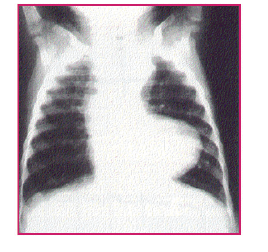

Uma criança de 2 anos chega para consulta no ambulatório de cardiologia pediátrica com quadro de cianose e dispneia. Durante a investigação diagnóstica foi solicitada radiografia de tórax, cuja imagem está a seguir:

Após analisar essa imagem, associando ao quadro clínico apresentado, devemos suspeitar da seguinte patologia: